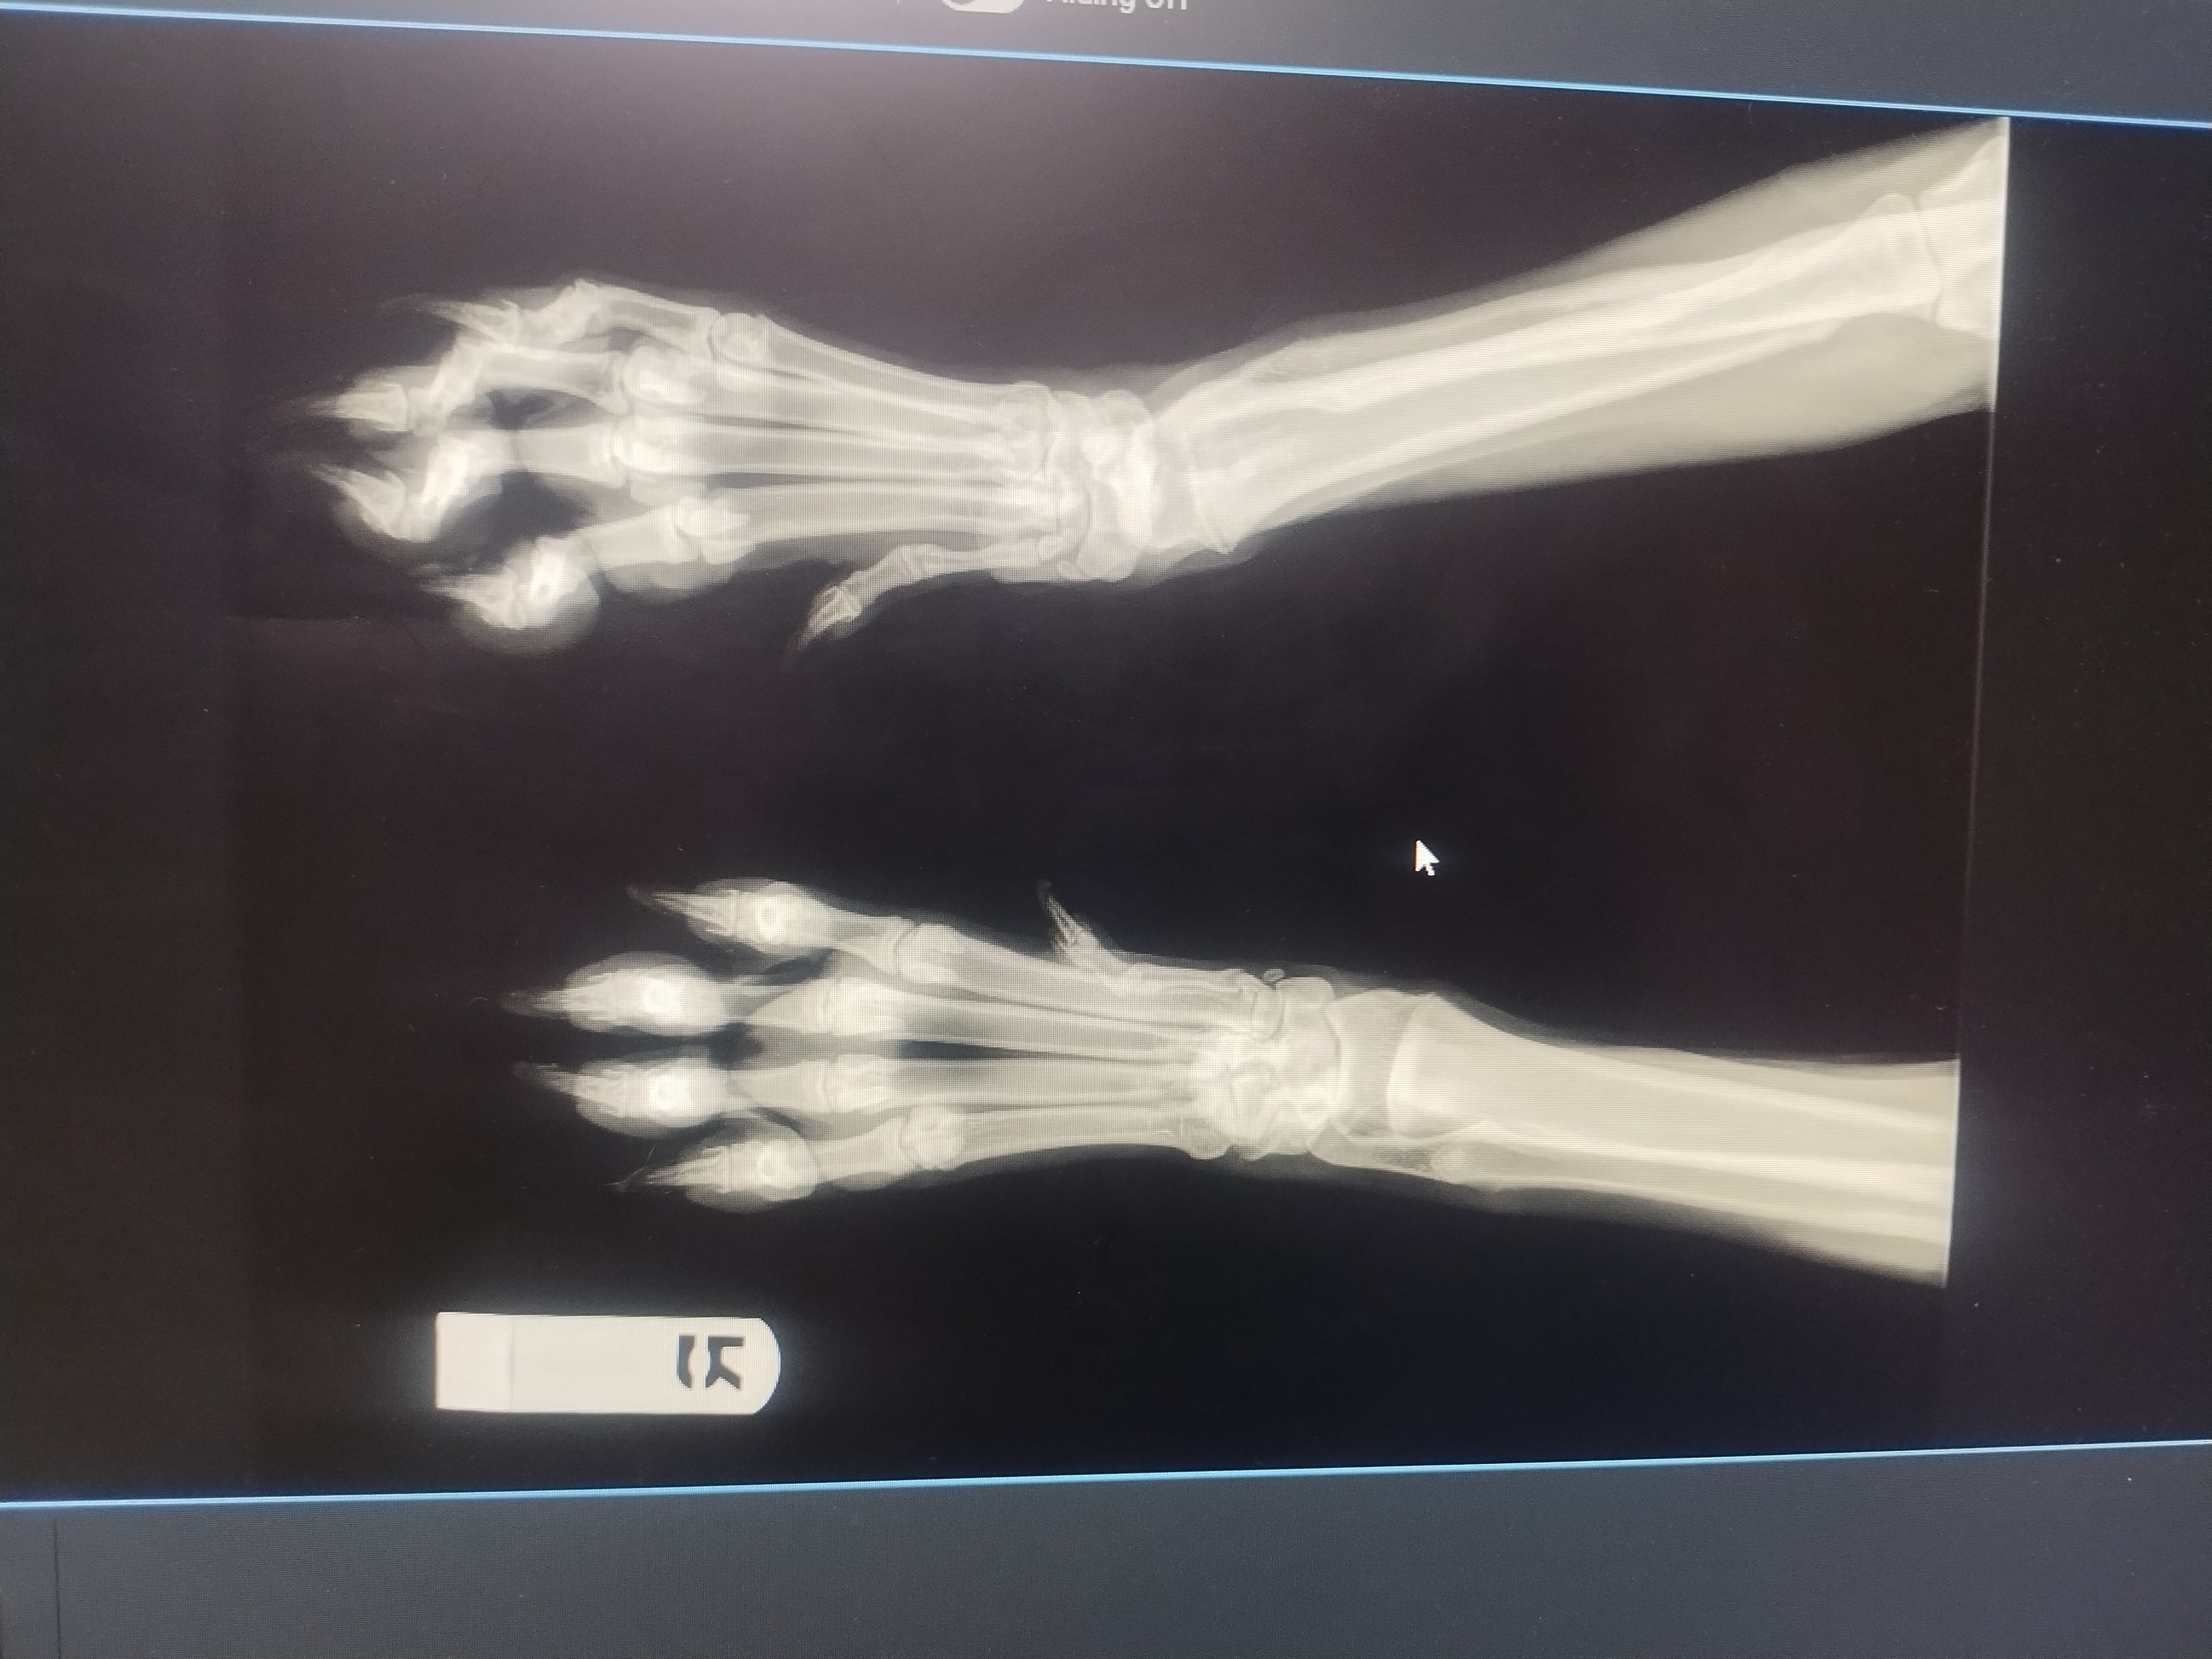

This is Oscar. He was a little trash can dog about to be sent to the animal shelter until I went and got him. Turns out, he was severely malnourished and chewed off all of his own toenails, and then developed a growth handicap. He's my short king, my gimp and I love him so, however, they're gonna have to break his leg to fix his growth plate. He'll probably never be the normal size of a German shepherd, but he's my perfect boy! Nothing holds his little stubborn butt back except his leg. But even that doesn't. He's still a pain in the ass haha, but if you know me, you know how I feel about my dogs and anything would help! I appreciate you all whether you just read his story, or whether you help us out with him! I will appreciate every share this gets, every donation, anything to help get my babe his surgery! Thanks everyone for taking the time to learn about him ♥️